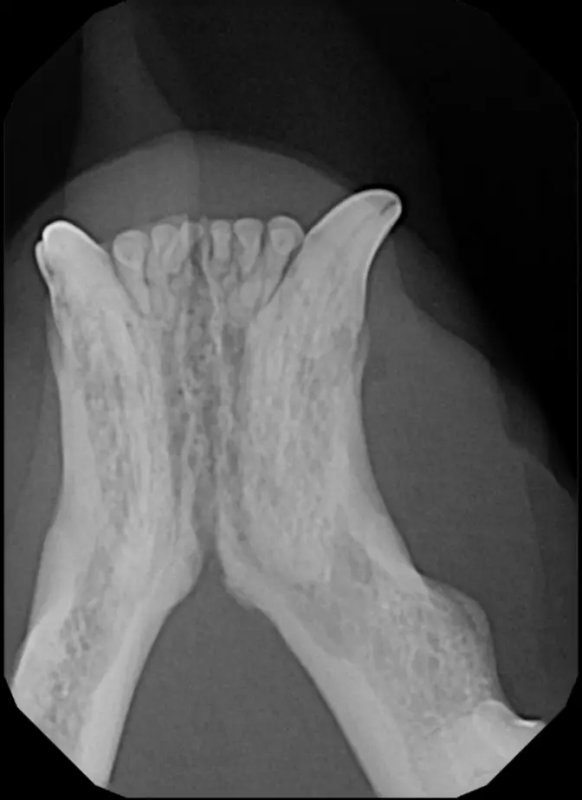

Tooth resorption is a disease process where the body begins to break down the adult tooth. It is widely known to occur in cats but can also occur in dogs. In cats these lesions are thought to be inflammatory, while in dogs they can be more of a replacement resorption process. These lesions can be very painful and should be treated, generally with extraction depending on the type of resorption that is occurring. The disease can be progressive and affect many teeth over several years. It is important to have regular checkups and yearly dental cleanings to monitor for these lesions.